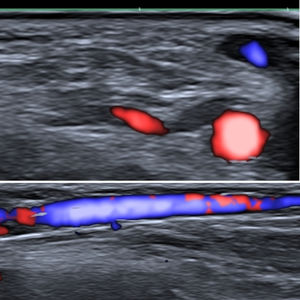

Fig. 1 shows the size of the cephalic vein and radial artery in the theoretical anatomical region of the implant (in a young man who we have taken as an example). As can be seen, both the artery and vein are large enough to be easily visible on ultrasound. This is obvious proof of the potential risks posed by these implants: they may become lodged in the vein, generating proximal migration, or they may cause local complications such as bleeding or hematoma due to venous (less likely due to the low blood pressure) or arterial (more likely because of the high pressure of the circuit) involvement.

Pulmonary embolisms are often difficult to diagnose because of their varied clinical presentation, the different nature of the embolized material, such as glues or coils, which constitute an important source of migrated materials, and the heterogeneous radiological signals they generate.8 As the use of these types of devices will presumably proliferate, there is likely to be an increase in the number of cases of pulmonary embolisms derived from implantation techniques. These procedures should be performed under medical supervision and should involve a mechanism for checking the extravascular location of the distal tip of the metal introducer prior to device release, including real-time ultrasound visualization. Ultrasound control may be difficult if proximal compression is not performed, given the low pressure of the venous system. As shown in Fig. 1, obtained under compression, both the vein and the artery are easily visible. This approach could ensure that the device is not placed intravascularly and that the vascular bed is unharmed; these precautions would without doubt increase the complexity of the implantation procedure but would clearly improve its safety. Another alternative would be to implant the device in a latero-lateral position, to avoid it following the main axis of the cephalic vein. It would be thus less likely to become lodged in a vein, substantially reducing or minimizing the risk of proximal pulmonary embolism.